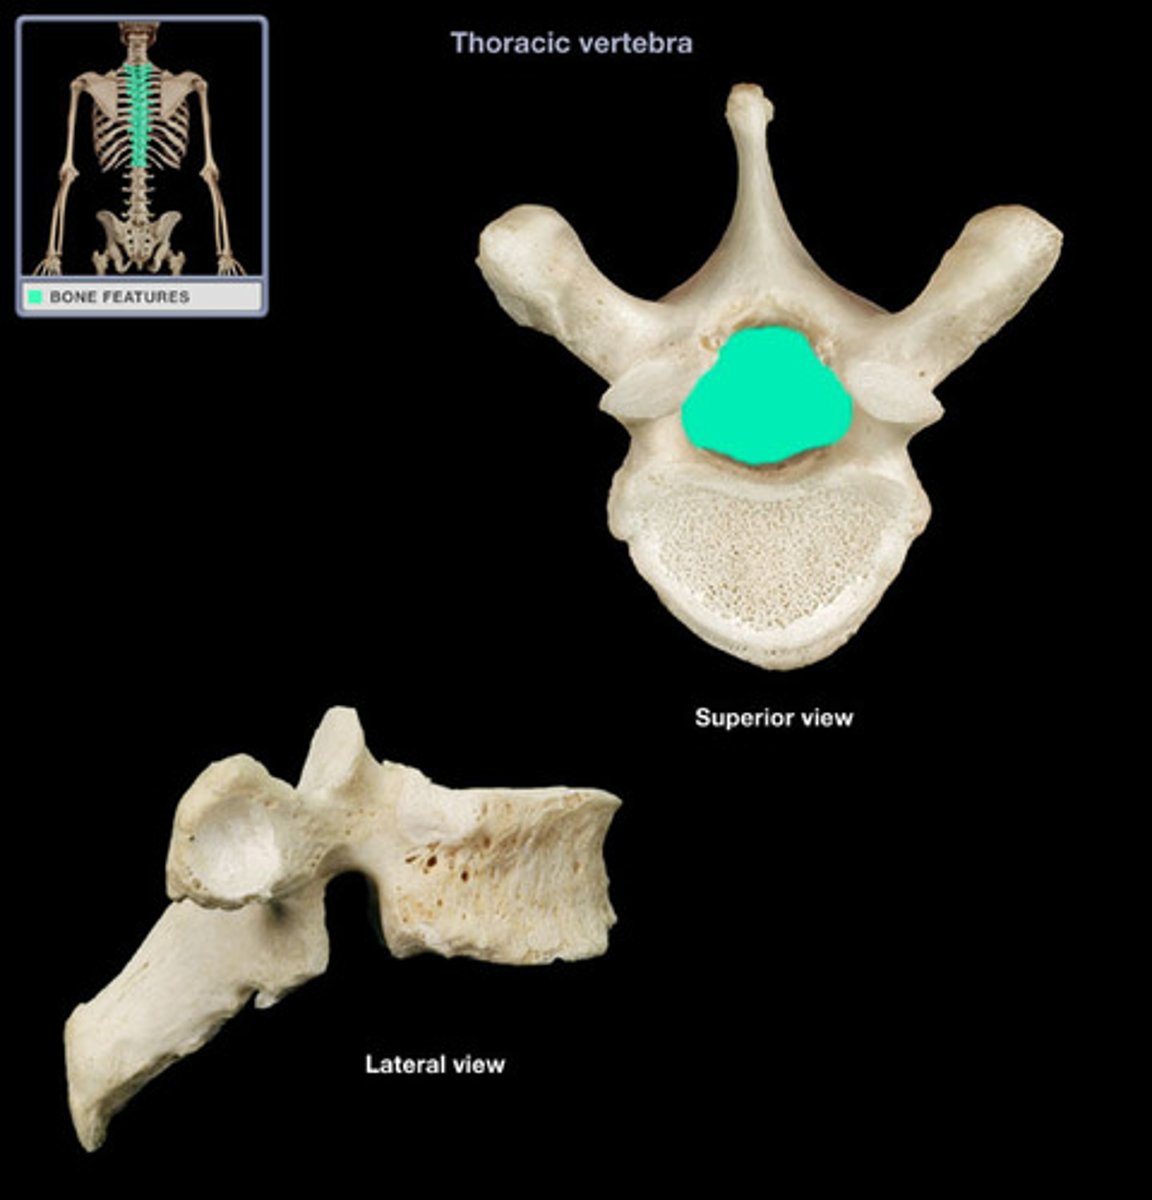

What are the two main parts a typical vertebra is composed of?

1. body

2. vertebral arch

The body and the vertebral arch enclose a space called the _________ _______

vertebral foramen

What is the unique characteristic of the thoracic spine?

facets for rib articulation